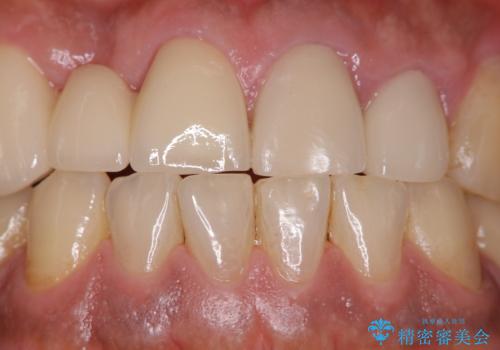

- イベントがあるため、なるべく綺麗にしたいとのことで来院されました。PMTC60分コースを行いました。

またPMTCを行うことで、ご自身本来の歯の色になり自然な明るさになります。

口元が自然な明るさになることで、より清潔感のある印象になるため行事やイベント前などにもPMTCを行うはおすすめです。